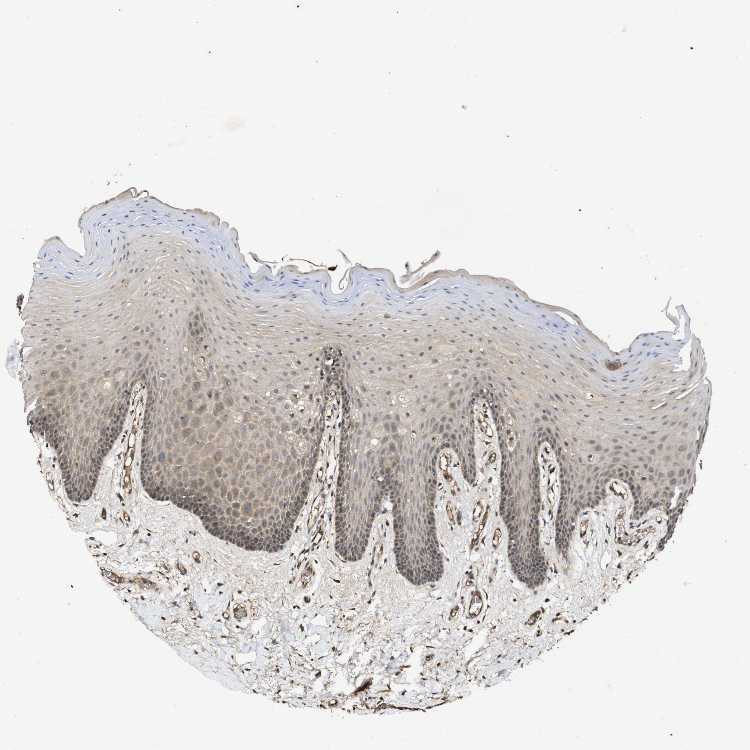

TISSUE PRIMARY DATA ORAL MUCOSA Show tissue menu

ORAL MUCOSA - Antibody stainingi

Antibody staining in the annotated cell types in the current human tissue is reported as not detected, low, medium, or high, based on conventional immunohistochemistry profiling in selected tissues. This score is based on the combination of the staining intensity and fraction of stained cells.

Each image is clickable and will lead to virtual microscopy that enables deeper exploration of all samples and also displays staining intensity scores, fraction scores and subcellular localization as well as patient and tissue information for each sample.

Antibody HPA015257Antibody CAB010302

Squamous epithelial cells MediumMedium